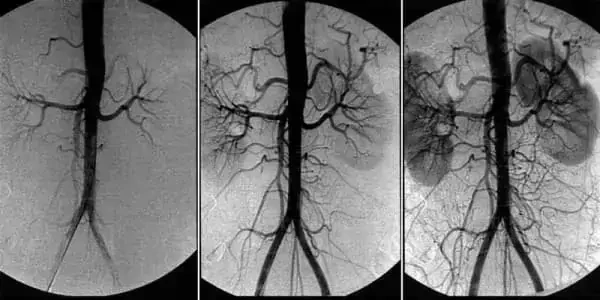

Ангиодистония сосудов головного мозга – это патологическое состояние, при котором нарушается тонус сосудов и нормальное кровообращение в тканях головного мозга. В этой статье вы сможете прочитать про её причины, механизмы и симптомы, при которых пора бить тревогу. А также про грозные осложнения этого коварного заболевания и про современный подход к лечению, доступный каждому.

Ангиодистония сосудов головного мозга влияет на работоспособность всего организма. Из-за неадекватного кровоснабжения мозга, снижается общая работоспособность, появляется слабость, а важные системы организма начинают работать со сбоями.